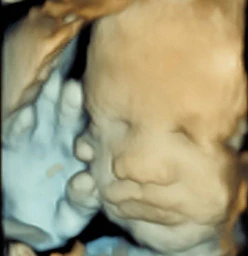

Specialised ultrasound services including 2D and Dynamic 4D scans- realistic imaging, Abdominal, Pelvic, Breast, Thyroid, Doppler scans. Dynamic 4D Scans are unique to ultrasound scan with exceptional clarity. View these remarkable images on our website. Read more

Having a baby is a wonderful and empowering experience. Genesis Maternity Clinic was founded in 2009 and our beautiful clinic is nestled in the leafy green suburb of Saxonwold, Johannesburg. The clinic offers professional and supportive maternity care throughout your pregnancy and the birth of your baby. We accept both private and medical aid patients. Our philosophy Genesis Clinic specialises in natural, low-risk pregnancies. We believe that pregnancy and birth should be a normal healthy... Read more